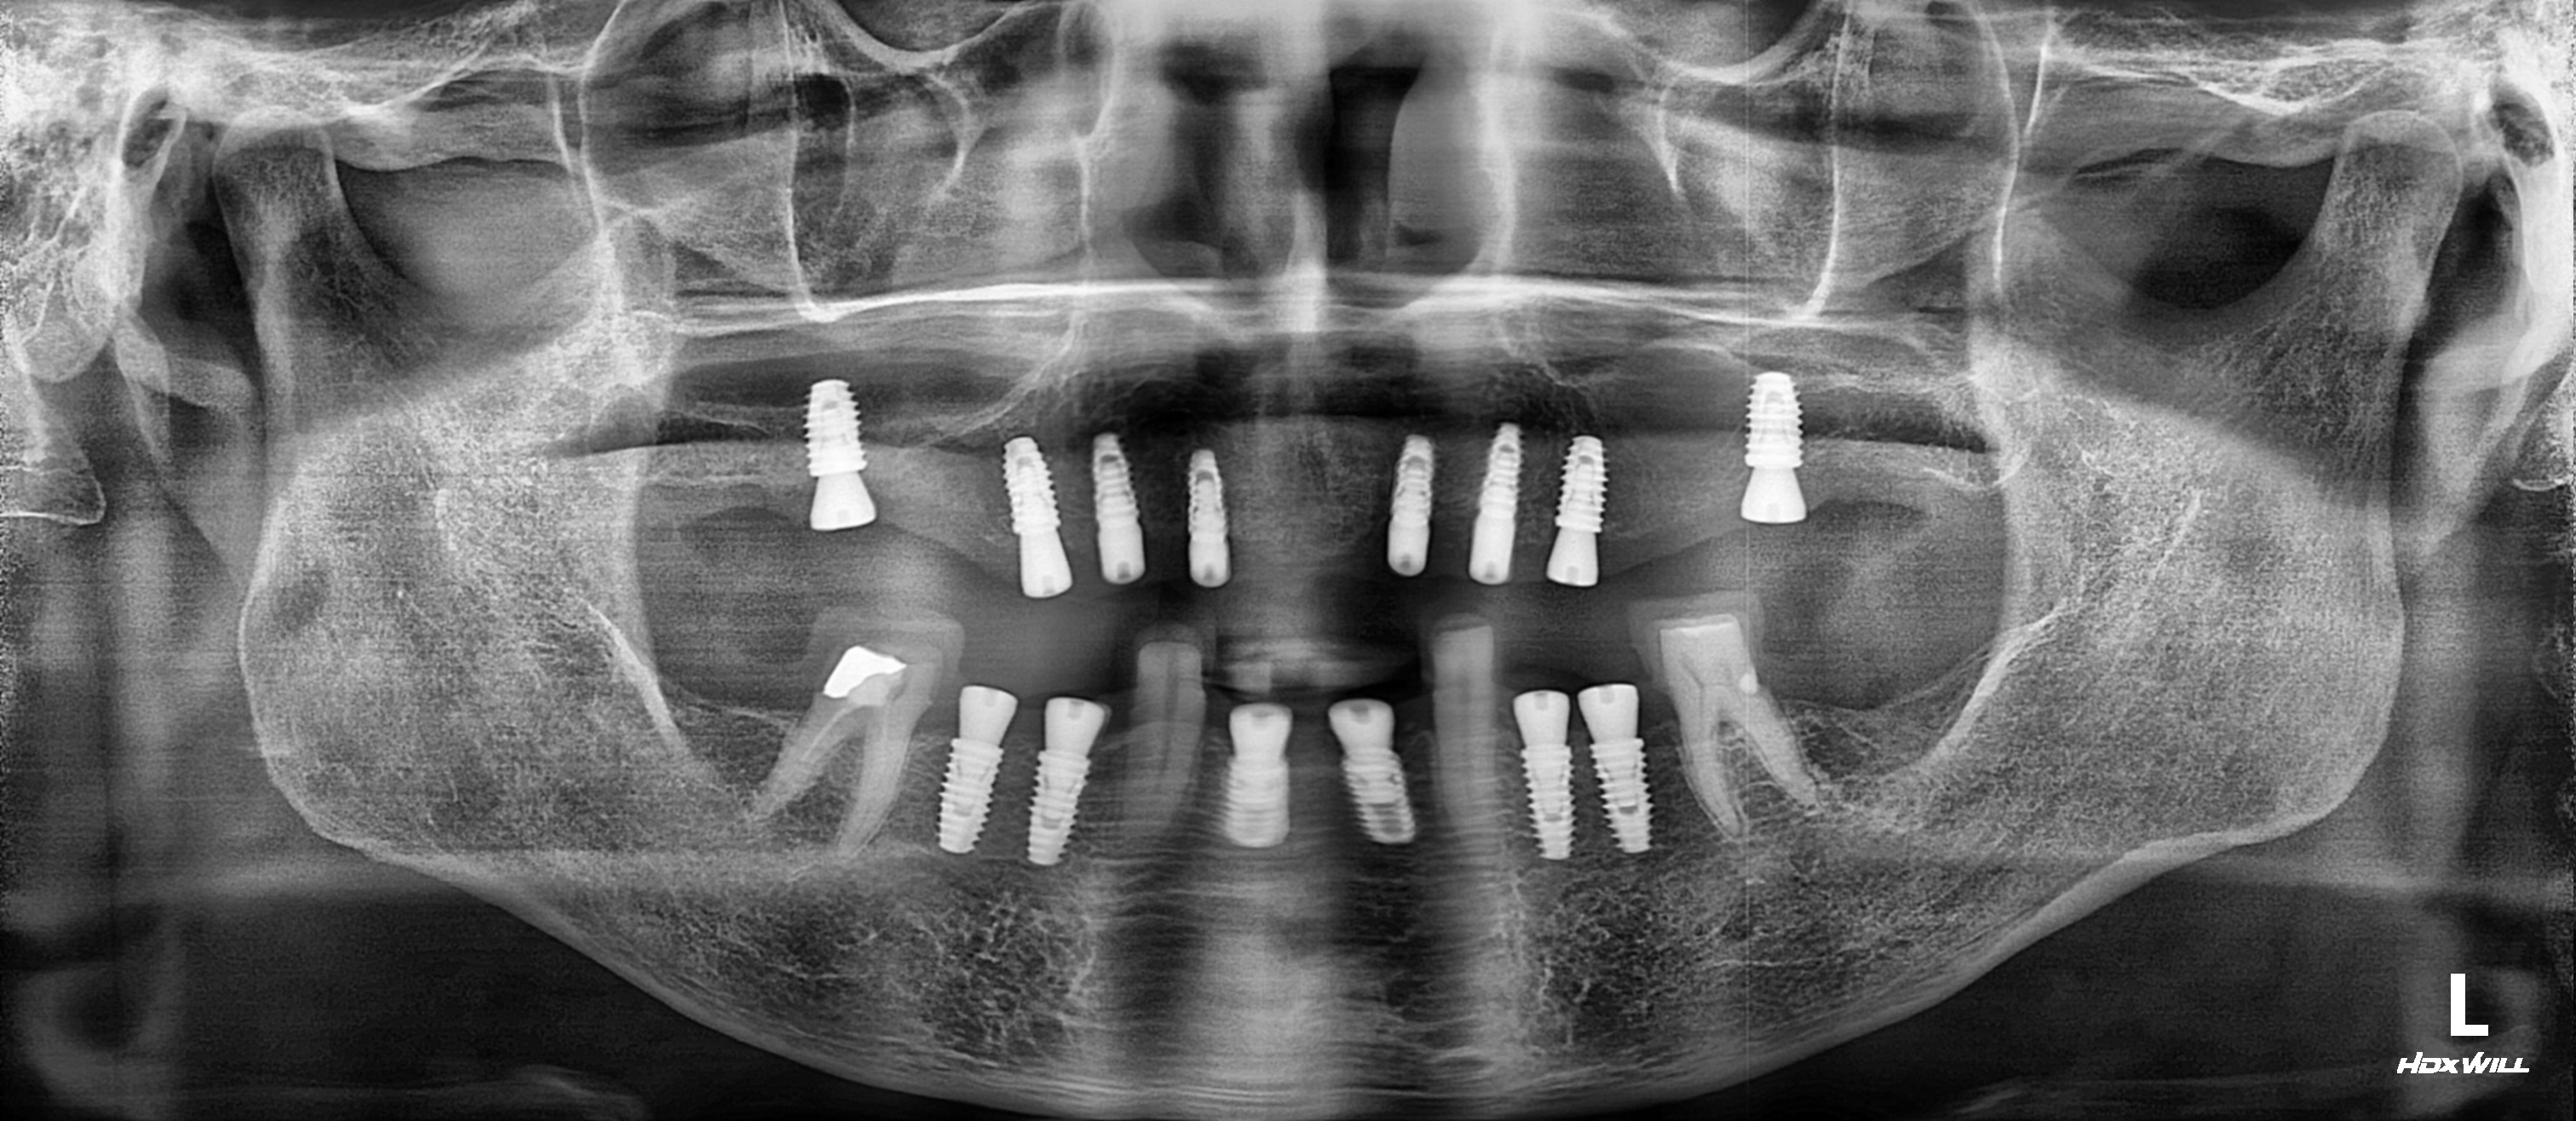

치료 후 파노라마

상악은 윗니 상태가 매우 좋지 않아 전악 8개를 식립하였습니다.

하악은 살릴 수 있는 치아는 충치를 치료하여 크라운 수복하고, 임플란트를 이용해 교합과 저작을 완성하였습니다.